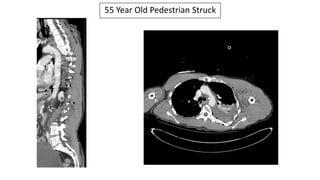

55 Year Old

Pedestrian Struck

Wide Mediastinum

Tracheal Deviation

And Loss Of The

Aortopulmonary

Window

Traumatic Aortic Disruption & Multiple Rib Fractures

55 Year Old Pedestrian Struck

Traumatic Aortic Disruption

Successfully

Deployed TEVAR

Multiple Posterior Rib Fractures